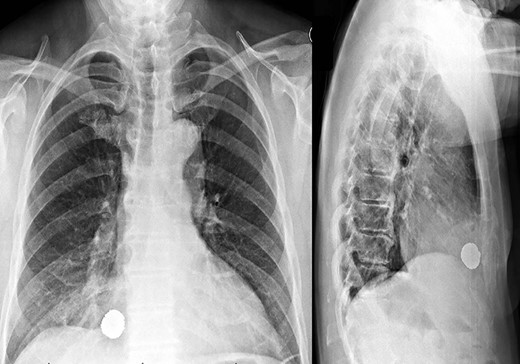

Initial anteroposterior and lateral chest X-rays of the patient, consistent with intrathoracic penetration of the bean bag foreign body.

A 59-year-old man was transferred acutely from another hospital for evaluation of a penetrating thoracic injury. The patient reportedly had been shot twice with a bean bag gun and sustained injuries to the right chest and flank during an altercation with police officers. The patient was breathing comfortably and normotensive, and his GCS was 15. He had a history of unprovoked pulmonary embolism and was taking apixaban. There was a 2-cm circular wound through the skin just superior to the right nipple and a 5-cm area of ecchymotic but intact skin over the right flank. A chest X-ray showed a 2-cm object with metallic density overlying the right thoracic cavity (Fig. 1). A chest CT showed the object in close proximity to the right atrium, right internal mammary artery and right middle lobe (Fig. 2). Additionally, a small amount of effusion consistent with hemothorax was present, for which a chest tube was placed. The patient was admitted for chest tube management and pain control, on the assumption that the metallic foreign body did not warrant operative removal.